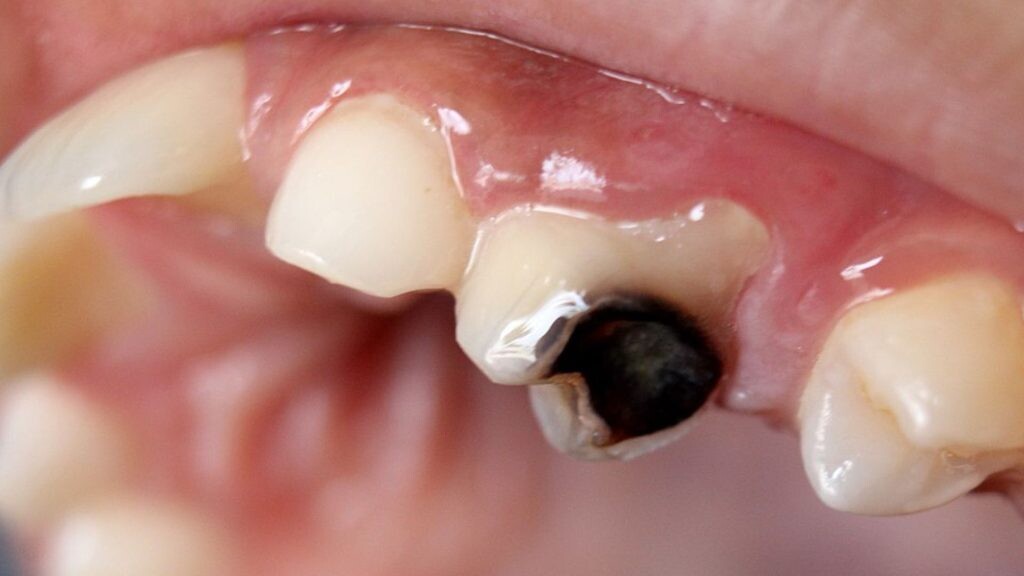

Enamel Damage can result in black teeth

Decay or cavities are the most common reason for teeth turning black. When the pulp becomes infected, the black color begins inside the tooth and works its way to the surface. The black appearance often starts as a few dark spots, but when left untreated, the whole tooth can turn black. Turning black is usually a gradual transformation that begins with brown or gray spots or small dots of black near the gum line.

An injury to the mouth can damage the tooth so badly that it dies, in which case the tooth may also turn black.

Tartar and Stains

Tartar that develops on the outside of the molars or inside the front teeth can build up stains and erode holes in the teeth and make them look black.